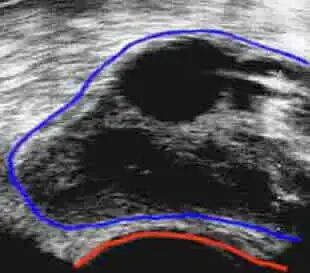

卵子在卵巢中充满液体的结构-卵泡中,每个卵泡都可以通过超声波进行观察和测量。

(超声照片显示受刺激的卵巢中的多个卵泡(黑色结构))